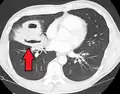

A subpleural abscess.